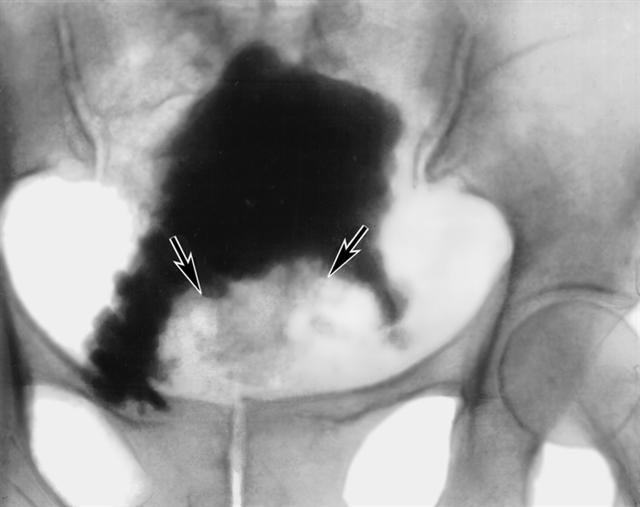

Рис. 4. Цистограмма при раке мочевого пузыря: стрелками указан крупный очаг поражения в области шейки мочевого пузыря.